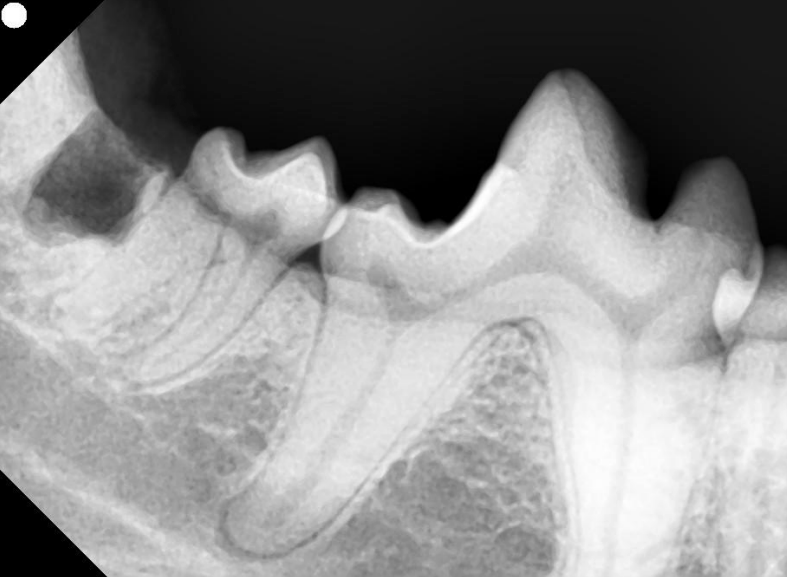

全身麻酔を行い、歯科専用レントゲン撮影と口腔内の評価をしたところ、右下顎第3後臼歯に「埋伏歯(まいふくし)」が確認されました。

赤丸部分 埋伏歯

初期の場合は症状がほとんどないため、埋伏歯があるかどうかは歯科用のレントゲン検査を実施して判明することが多いです。

埋伏歯は口の中を見ただけでは判断が難しいため、歯科レントゲンによる画像診断が不可欠です。歯の位置や形、周囲の骨の状態を確認することで、治療の必要性や方法を判断します。